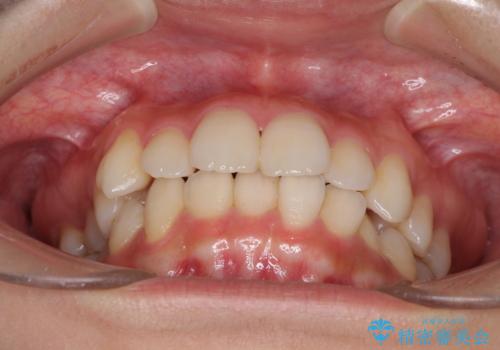

- 前歯のデコボコを気にして来院された患者様です。

叢生と捻転が随所に認められるものの、マウスピースで十分対応可能であったため、インビザラインにて矯正治療を行うこととしました。

マウスピース矯正は毎日しっかりと装着することがとても大切です。

こちらの方はしっかりと指示を守って装着してくださったため、予定通り治療を終えることができました。